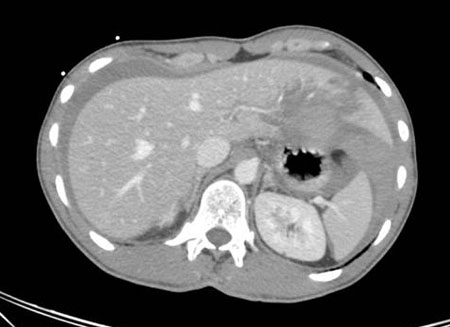

Lesão renal

história de lesão contusa ou penetrante no flanco; queda com rápida desaceleração ou acidente com veículo automotor; hematúria macroscópica; dor no abdome e no flanco, principalmente na inspiração

Exame físico

feridas penetrantes e/ou contusões no flanco ou costas; fraturas da 11ª ou 12ª costela; sensibilidade no flanco; hematúria macroscópica; dor no abdome/flanco pior à inspiração; sensibilidade no ângulo costovertebral; instabilidade hemodinâmica

Primeira investigação

Outras investigações